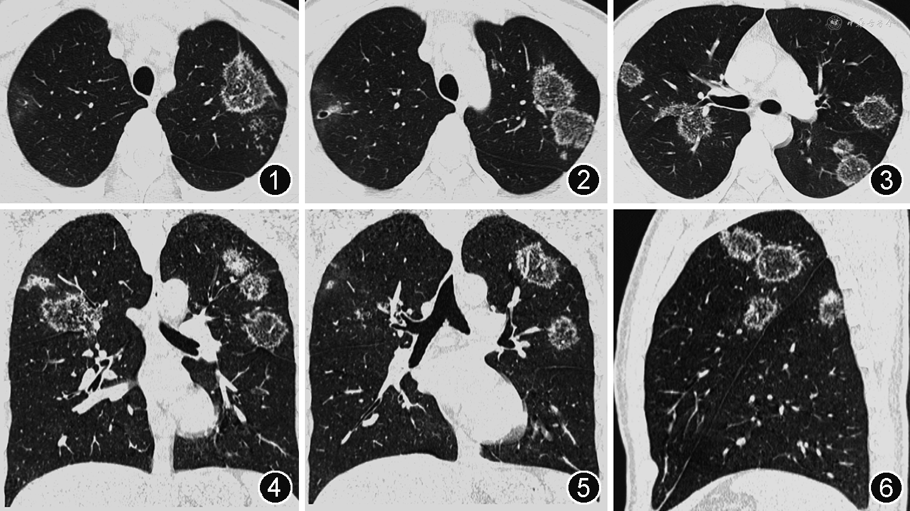

入院后查血常规:淋巴细胞计数1.057×109/L(正常参考值1.10~3.20×109/L),余正常;九项呼吸道感染病原体IgM抗体:抗肺炎支原体IgM抗体(+);肿瘤标志物:神经元特异性烯醇化酶(NSE)36.20 μg/L(正常参考值≤20.0 μg/L);抗核抗体谱:抗SSA抗体(+++),抗Ro-52抗体(+++);抗核抗体:核颗粒型1∶320(+)。大小便常规、肝肾功能、静脉血葡萄糖、电解质、凝血功能、细胞免疫功能、感染性疾病筛查均正常。血清(1,3)-β-D葡聚糖(G试验)、半乳甘露聚糖(GM试验)、抗中性粒细胞胞质抗体(ANCA)以及诱导痰细菌和真菌涂片及培养、抗酸杆菌涂片均为阴性。新型冠状病毒核酸阴性。床旁心电图:窦性心律,正常心电图。胸部CT:双肺多发大小不等斑片影,中央为磨玻璃密度影,边缘为环状高密度影,呈反晕征;病灶内可见多发微结节堆积,呈结节状反晕征(图1, 2, 3, 4, 5, 6)。支气管镜检查:支气管黏膜呈炎症表现,气管腔内可见少许白色泡沫痰,未见狭窄及新生物。双上肺BALF送检细菌和真菌培养、涂片查抗酸杆菌、分枝杆菌核酸(TB/NTM-DNA)和Xpert MTB/RIF均为阴性;BALF液基制片:未查见癌瘤细胞。于右上叶后段行黏膜活检术,病理示黏膜慢性炎症。(2023年2月22日)行CT引导下左上肺病灶穿刺活检术,病理示慢性肉芽肿性炎(图7),未查见抗酸杆菌。患者有口干症状,抗SSA抗体、抗Ro-52抗体强阳性,考虑干燥综合征可能,给予完善唇腺活检,病理示:送检唇腺内查见淋巴组织浸润>1灶,活检分级为Ⅳ级。患者干燥综合征诊断明确,但双肺多发反晕征是由活动性肺结核还是干燥综合征继发机化性肺炎(OP)导致仍不能确定。多学科诊疗团队(MDT)讨论后认为:患者青年男性,免疫功能正常,肺部病变以双上肺分布为主,表现为多发反晕征伴微结节堆积,与典型OP环壁光滑的反晕征不符,且TSPOT.TB呈阳性,病理见肉芽肿形成,高度怀疑为活动性肺结核;但结节病、干燥综合征继发的其他肺损害亦不能完全排除,建议病理组织完善结核分枝杆菌聚合酶链反应(TB-PCR)检测,必要时在征得患方同意后可予诊断性抗结核治疗。(2023年3月1日)病理组织外送TB-PCR(成都中医药大学附属医院):TB-DNA(+)。最终诊断:活动性肺结核合并干燥综合征。因患者无多系统受累表现,故仅给予标准四联方案抗结核治疗,未使用糖皮质激素或免疫抑制剂,嘱其至传染病医院及风湿免疫科门诊随诊。1个月后电话随访患者,诉其正接受抗结核治疗。遗憾的是,目前未能与患者取得再次联系,故未能知晓其治疗转归。

结节状反晕征(nodular reverse halo sign,NRHS)是反晕征中相对特殊的类型,即在反晕征的环壁和(或)环内出现了弥漫分布的微结节,这些微结节在组织学上与肉芽肿相对应[3]。国内学者亦将这种成簇状堆积的小叶中心性微结节命名为“烟花征(fireworks sign)”,并根据局部堆积的微结节数量差异将烟花征分成了晕征样、反晕征样和均匀样3种不同的影像学表现形式[4]。NRHS的出现可以将反晕征的鉴别诊断范围缩小至结核病、结节病、副球孢子菌病和隐球菌病等肉芽肿性疾病中。(1)肺结核的影像可表现为小叶中心性结节、树芽征、支气管壁增厚、实变、空洞、斑片影、磨玻璃影等,病灶呈多形态、多部位、多钙化的特点;NRHS是肺结核的少见征象,多出现在免疫功能正常的青年患者,一般缺少临床症状,且常规病原学检查常为阴性[5],这些特征均与本例患者相符。(2)结节病是一种病因不明的、以非干酪样坏死性肉芽肿形成为病理特征的系统性肉芽肿性疾病;其典型影像表现为双侧对称的肺门或纵隔淋巴结增大,肺实质受累时可表现为多发沿淋巴管周围(支气管血管束、叶间裂、胸膜)分布的小结节[6];部分结节病可以出现NRHS,但多伴随有其他相对典型的征象[7]。(3)副球孢子菌病是拉丁美洲、巴西郊区最常见的真菌病;其影像表现多样,可以为结节、空洞、磨玻璃影、支气管血管周围间质增厚、支气管壁增厚、牵拉性支气管扩张和瘢痕旁肺气肿[7]等,约20%的病例可伴随出现NRHS。(4)肺隐球菌病是因吸入隐球菌孢子而引起的肺深部真菌病;影像学表现为单发或多发的结节、肿块、实变、磨玻璃影、空洞等,可伴有晕征,病变以胸膜下分布为主[8];有极少数的肺隐球菌病例可以出现NRHS。